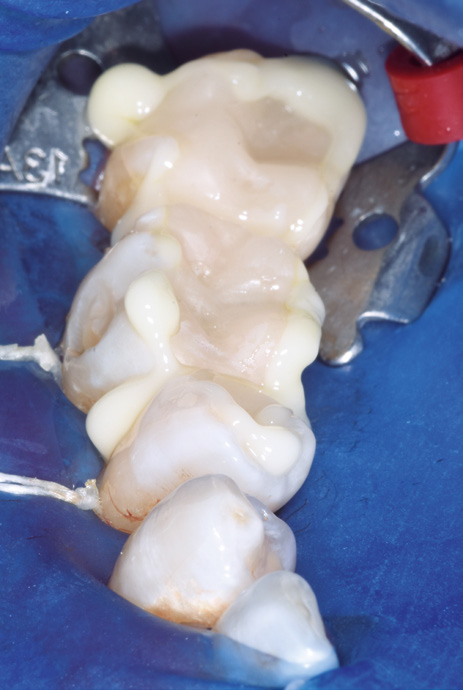

Close-up of dental impressions on a mold with white dental material filling cavities. The image includes a blue background and metal brackets.

Right after placement — cement excess stays put for easy excess clean-up.